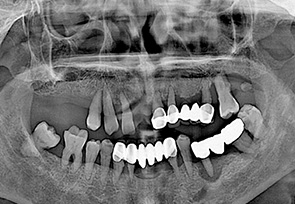

before

after